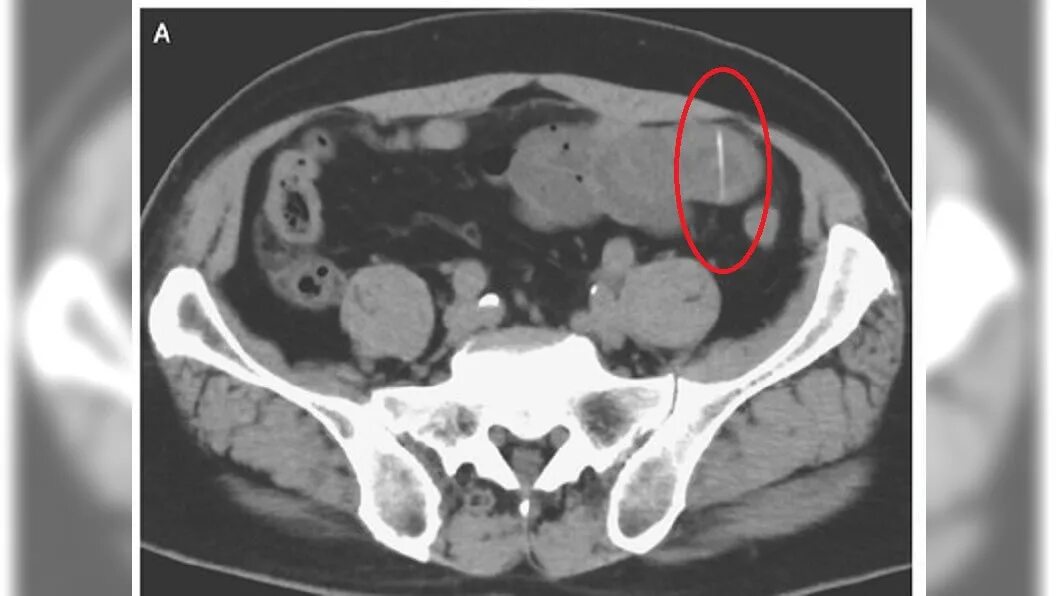

Как достать косточку из горла